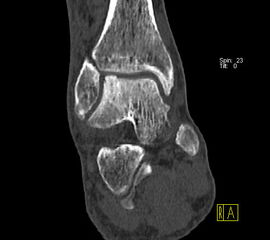

Die Kombination von SPECT und CT in einem Untersuchungsgang bringt wie bereits oben erwähnt eine erhöhte Ortsauflösung und artefaktfreie Darstellung von Knochenstoffwechselveränderungen der SPECT bei gleichzeitig excellent guter anatomischer Darstellung/Zuordnung durch die CT 3. Auf die Vorteile der CT gegenüber dem konventionellen Röntgen muss nicht mehr besonders eingegangen werden. Besonders eignet sich die „SPECT-CT“ zur Diagnostik von Fußerkrankungen (Biersack HJ et al. 2012).

Aufgrund der optimalen funktionellen Darstellung (PET) und der entsprechend guten anatomischen Bildgebung kann dieses kombinierte Untersuchungsverfahren viele Fragestellungen auch im Bereich des Fußes beantworten. Exemplarisch werden folgende Indikationen erwähnt. Abklärung von Infektionen im muskuloskelettalen Bereich 45, Untersuchungen von unklaren Fußschmerzen (Biersack HJ et al. 2012), präoperative Bildgebung beim Charcot-Fuß/diabetischer Fuß 31.